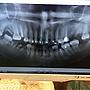

[問題] 植牙與矯正的問題 (附圖已刪文

[ teeth_salon ]12 留言, 推噓總分: +2

作者: HagganDazs - 發表於 2019/04/12 05:32(6年前)

9FHagganDazs: 謝謝大家的回覆 如果不考量預算04/12 14:43

10FHagganDazs: 是不是應該要植好所有缺牙04/12 14:43

11FHagganDazs: 長遠來說才是好的方針呢04/12 14:44

12FHagganDazs: 台大植牙一顆十萬 勒緊褲帶衝了qq04/12 14:44